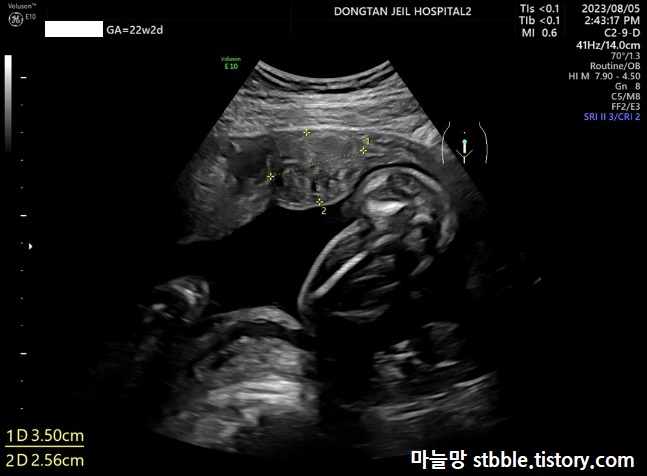

1. 아기 머리직경 (BPD)

아기 머리직경을 잽니다.

아기 머리 직경을 재고 있어요. 22주 2일에 5.36cm 이예요. 머리 직경은 크지도 작지도 않고 주수대로 잘 자라고 있는 듯 보입니다.